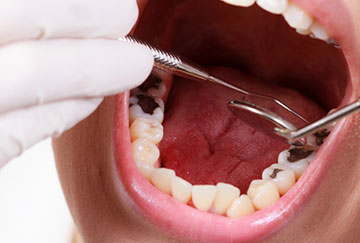

Caries